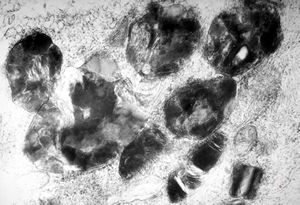

M, 48y. | Fabry disease - myocardium

M, 48y. | Fabry disease - cornea